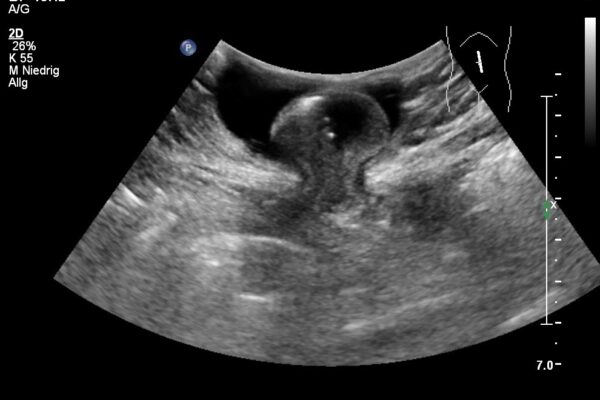

Die Bildgebung mittels Ultraschall (Sonographie) ist die am meisten genutzte, bildgebende Technik in der medizinischen Diagnostik. Dabei werden Schallwellen mit Frequenzen zwischen 1 und 40MHz benutzt. Die Ultraschallsonde (Schallkopf) sendet kurze Schallwellen aus, die im untersuchten Gewebe unterschiedlich stark reflektiert werden. Die reflektierten Schallsignale werden von der Ultraschallsonde wieder empfangen und vom Ultraschallgerät in Grauwerte auf dem Monitor dargestellt. So entsteht ein Ultraschallbild der inneren, von aussen nicht sichtbaren Organe und Strukturen. Dabei sind alle soliden oder blutreichen Organe (wie zB. Leber, Gallenblase, Nieren, Schilddrüse) und viele Gelenke (wie zB. Schulter, Knie, Hände und Füsse) gut untersuchbar.

Im Ultraschall der Bauchhöhle beurteilt der Arzt die Grösse, die Struktur und die Lage der Bauchorgane und Gefässe.

Duplex- und Dopplersonographien sind spezielle Ultraschalluntersuchungen, mit denen Arterien und Venen, also Blutgefässe, beurteilt werden können. Der Schallkopf sendet Wellen in einer bestimmten Frequenz aus, die Wellen werden von den Blutkörperchen und den Gefässwänden in einer veränderten Frequenz reflektiert. Diese Veränderungen der Frequenzen hängen u.a. von der Bewegung der Blutkörperchen ab. Dadurch kann die Richtung des Blutflusses und die Fliessgeschwindigkeit des Blutes bestimmt werden. Dem Arzt ist es dadurch möglich, Einengungen (Stenosen) oder Verschlüsse von Blutgefässen zu erkennen. Die Methode ist völlig risikofrei und eignet sich zur Untersuchung sämtlicher Blutgefässe am Hals, an den Extremitäten (Arme und Beine) sowie im Bauchraum.